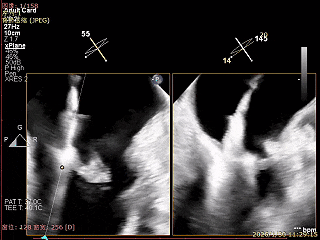

房间隔穿刺高度4.1cm

SGC穿房间隔进入左房

第一枚XTR进入左房

在1区进行轨迹测试和Orientation调整

将调整好的夹子移动至3区下左室

在左室打开夹子确认Orientation

捕捞瓣叶,确定瓣叶瓣尖稳定插入夹臂后,Gripper Down

Gripper Down后Bouncing明显